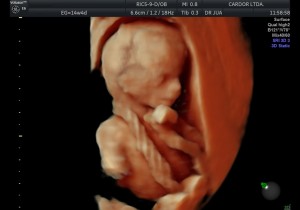

El desarrollo del feto varía en cada trimestre del embarazo.

Vea la siguiente presentación. Imágenes 100% Cardor: